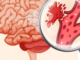

Типы и причины инсульта: обзор исходных факторов и разнообразия инсультов

Инсульт - это медицинское состояние, при котором возникают проблемы с кровоснабжением мозга. Это состояние может иметь разные типы и причины, но всегда требует немедленного...

ИНСУЛЬТ